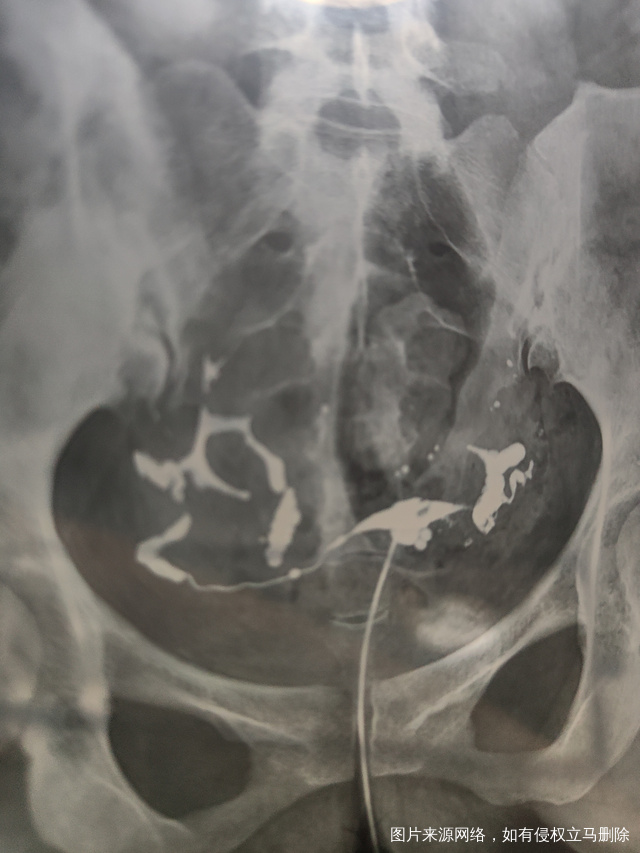

各位医生好前天做了输卵管造影请帮忙看看这些造